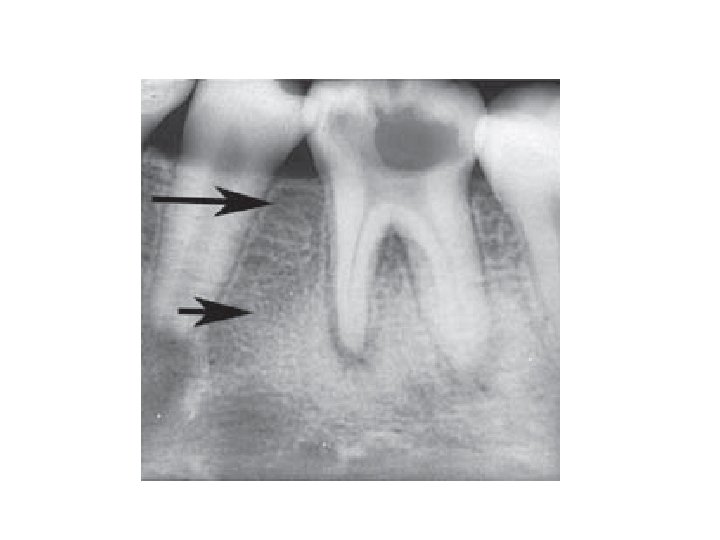

Peridontitis periapicalis chronica • Chronische Wurzelhautentzündung • Symptome: Es gibt sehr oft keine Symptome. • Röntgen: Periapikale Aufhellung-(Grenze ist nicht so scharf) Parodontalspaltverbreiterung

Parodontitis lateralis chronica • Es gibt Seitekanale nach mesiale oder nach distale Richtung. Die Veränderung erscheint neben der Wurzel. • Symptome: Keine Schmerzen, Devitalität des betroffenen Zahnes. • Röntgen: rundliche Aufhellung im lateralen Parodontium.